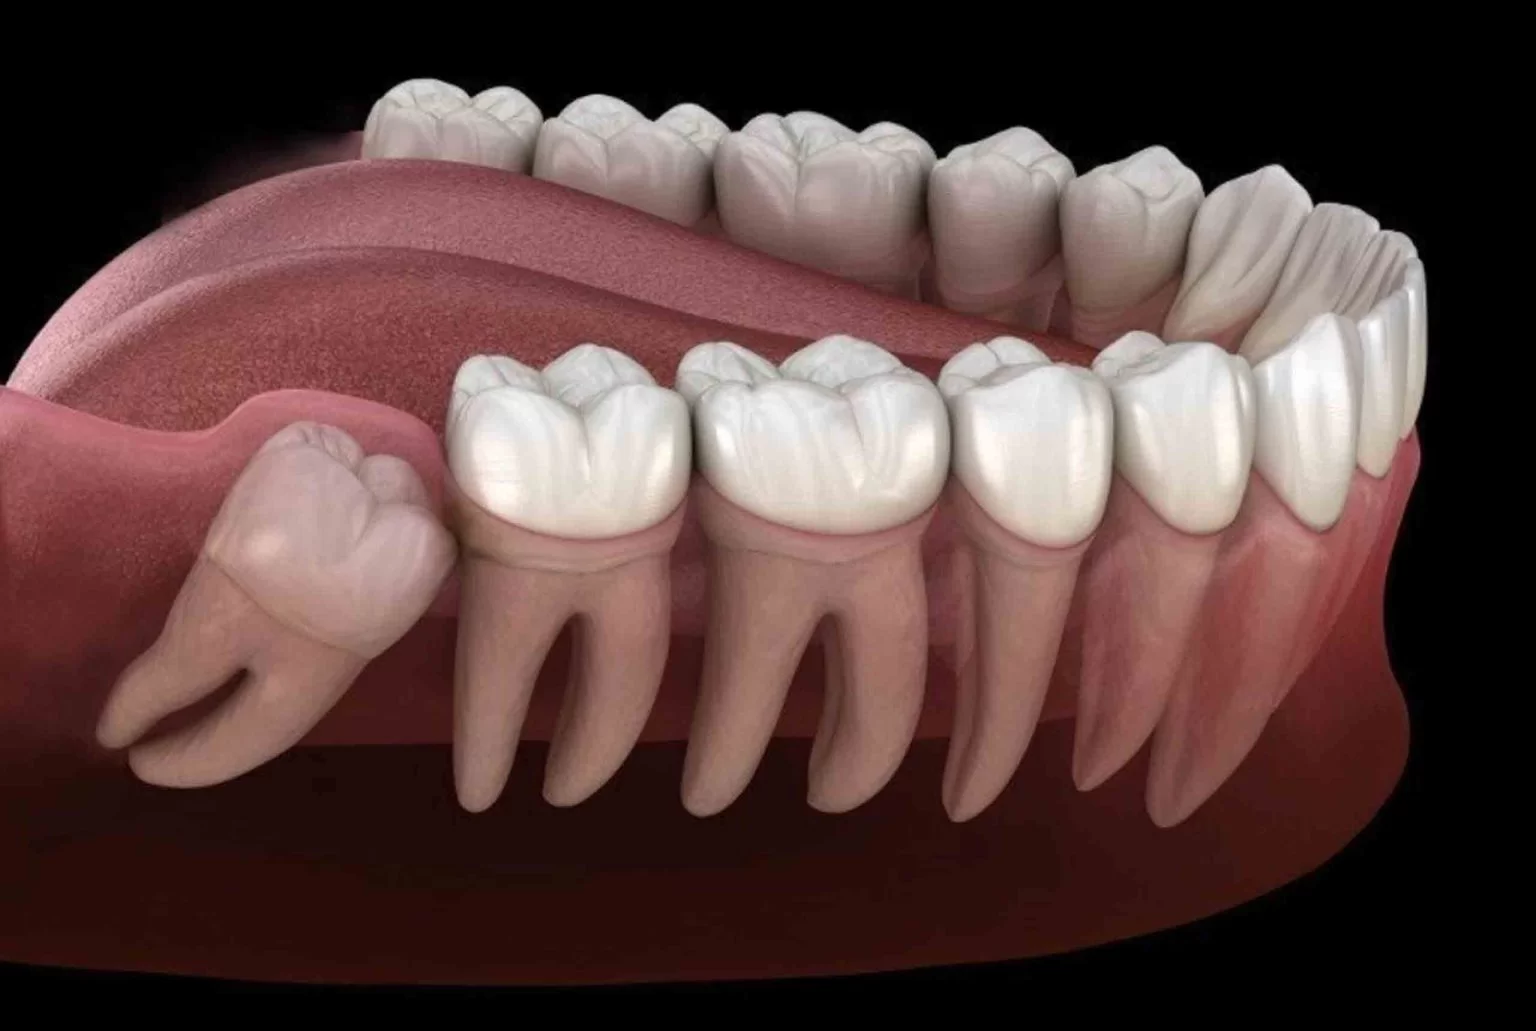

Wisdom teeth are the last set of molars to erupt. Removal is a common surgical procedure for teeth that are impacted (stuck beneath the gum line) or are causing crowding, pain, or recurrent infection in the back of the jaw.

Removing problematic wisdom teeth prevents serious issues such as shifting of other teeth, damage to adjacent molars, severe infection, and the formation of cysts or tumors in the jaw. It is a preventative measure for long-term oral health.

Same as Tooth Extraction: Stick to soft foods for several days. Avoid straws, smoking, spitting, and crunchy/chewy foods to ensure the surgical sites heal properly and to prevent the painful condition of dry socket.